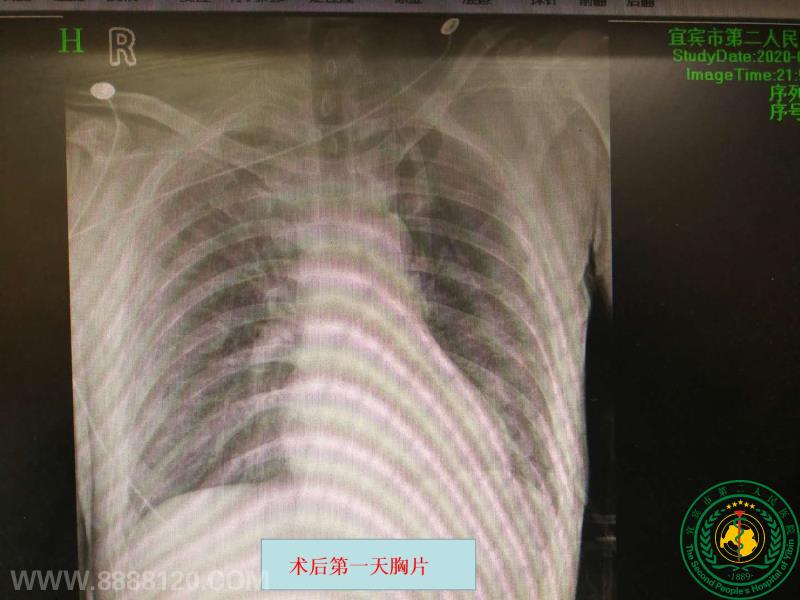

宜宾二医院率先在川中南独立成功开展胸腔镜辅助肺动脉支气管双袖式肺叶切除切除

宜宾二医院率先在川中南独立成功开展胸腔镜辅助肺动脉支气管双袖式肺叶切除切除26871